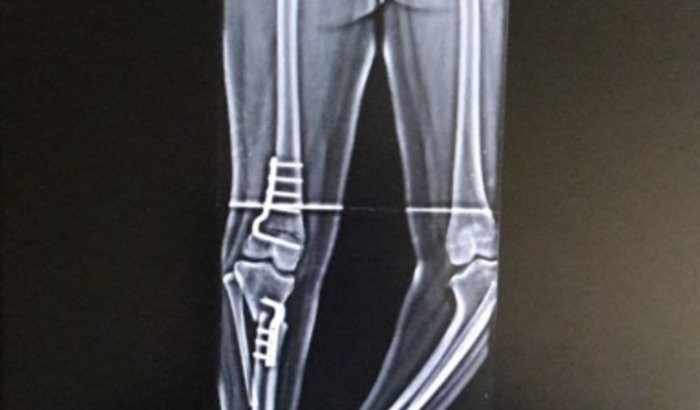

Oi, meu nome é Layslla, tenho 19 anos e resolvi fazer essa vakinha com propósito de conseguir arrecadar dinheiro para a minha cirurgia. Eu nasci com as duas pernas tortas, e graças a Deus eu consegui a minha primeira cirurgia na perna direita em 2017 pelo SUS. Essa imagem é de um raio-x que tirei logo após a cirurgia que foi feita.